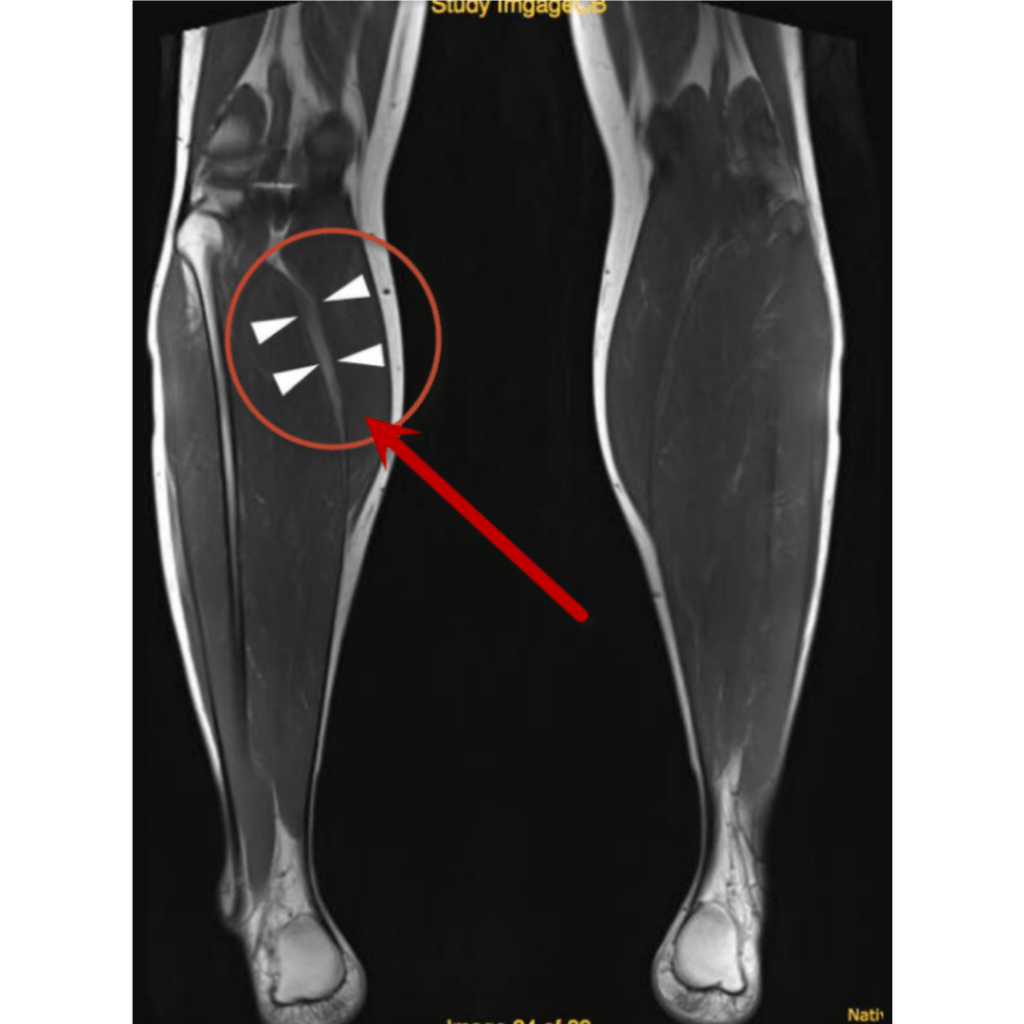

El diagnóstico de esta afectación dependerá mucho de su localización, en caso de sospecha de compromiso en un músculo superficial se puede hacer uso de ecografía (ultrasonido), en tejidos más profundos es más eficiente una resonancia magnética.

Resonancia magnética

Ruptura parcial Grado II

Un desgarro de segundo grado en el gemelo medial (músculo de la parte interna de la pantorrilla) el cual no necesito un tratamiento quirúrgico.Por lo que fue referido para su recuperación con terapia física.